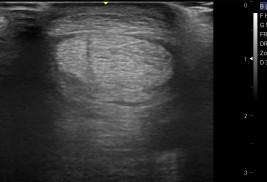

- modernen Ultraschallgeräten